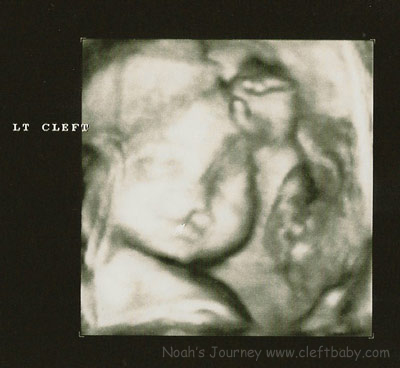

We found out at the 20 week ultrasound that Noah would

be born with at least a unilateral cleft lip and maybe a cleft

palate.